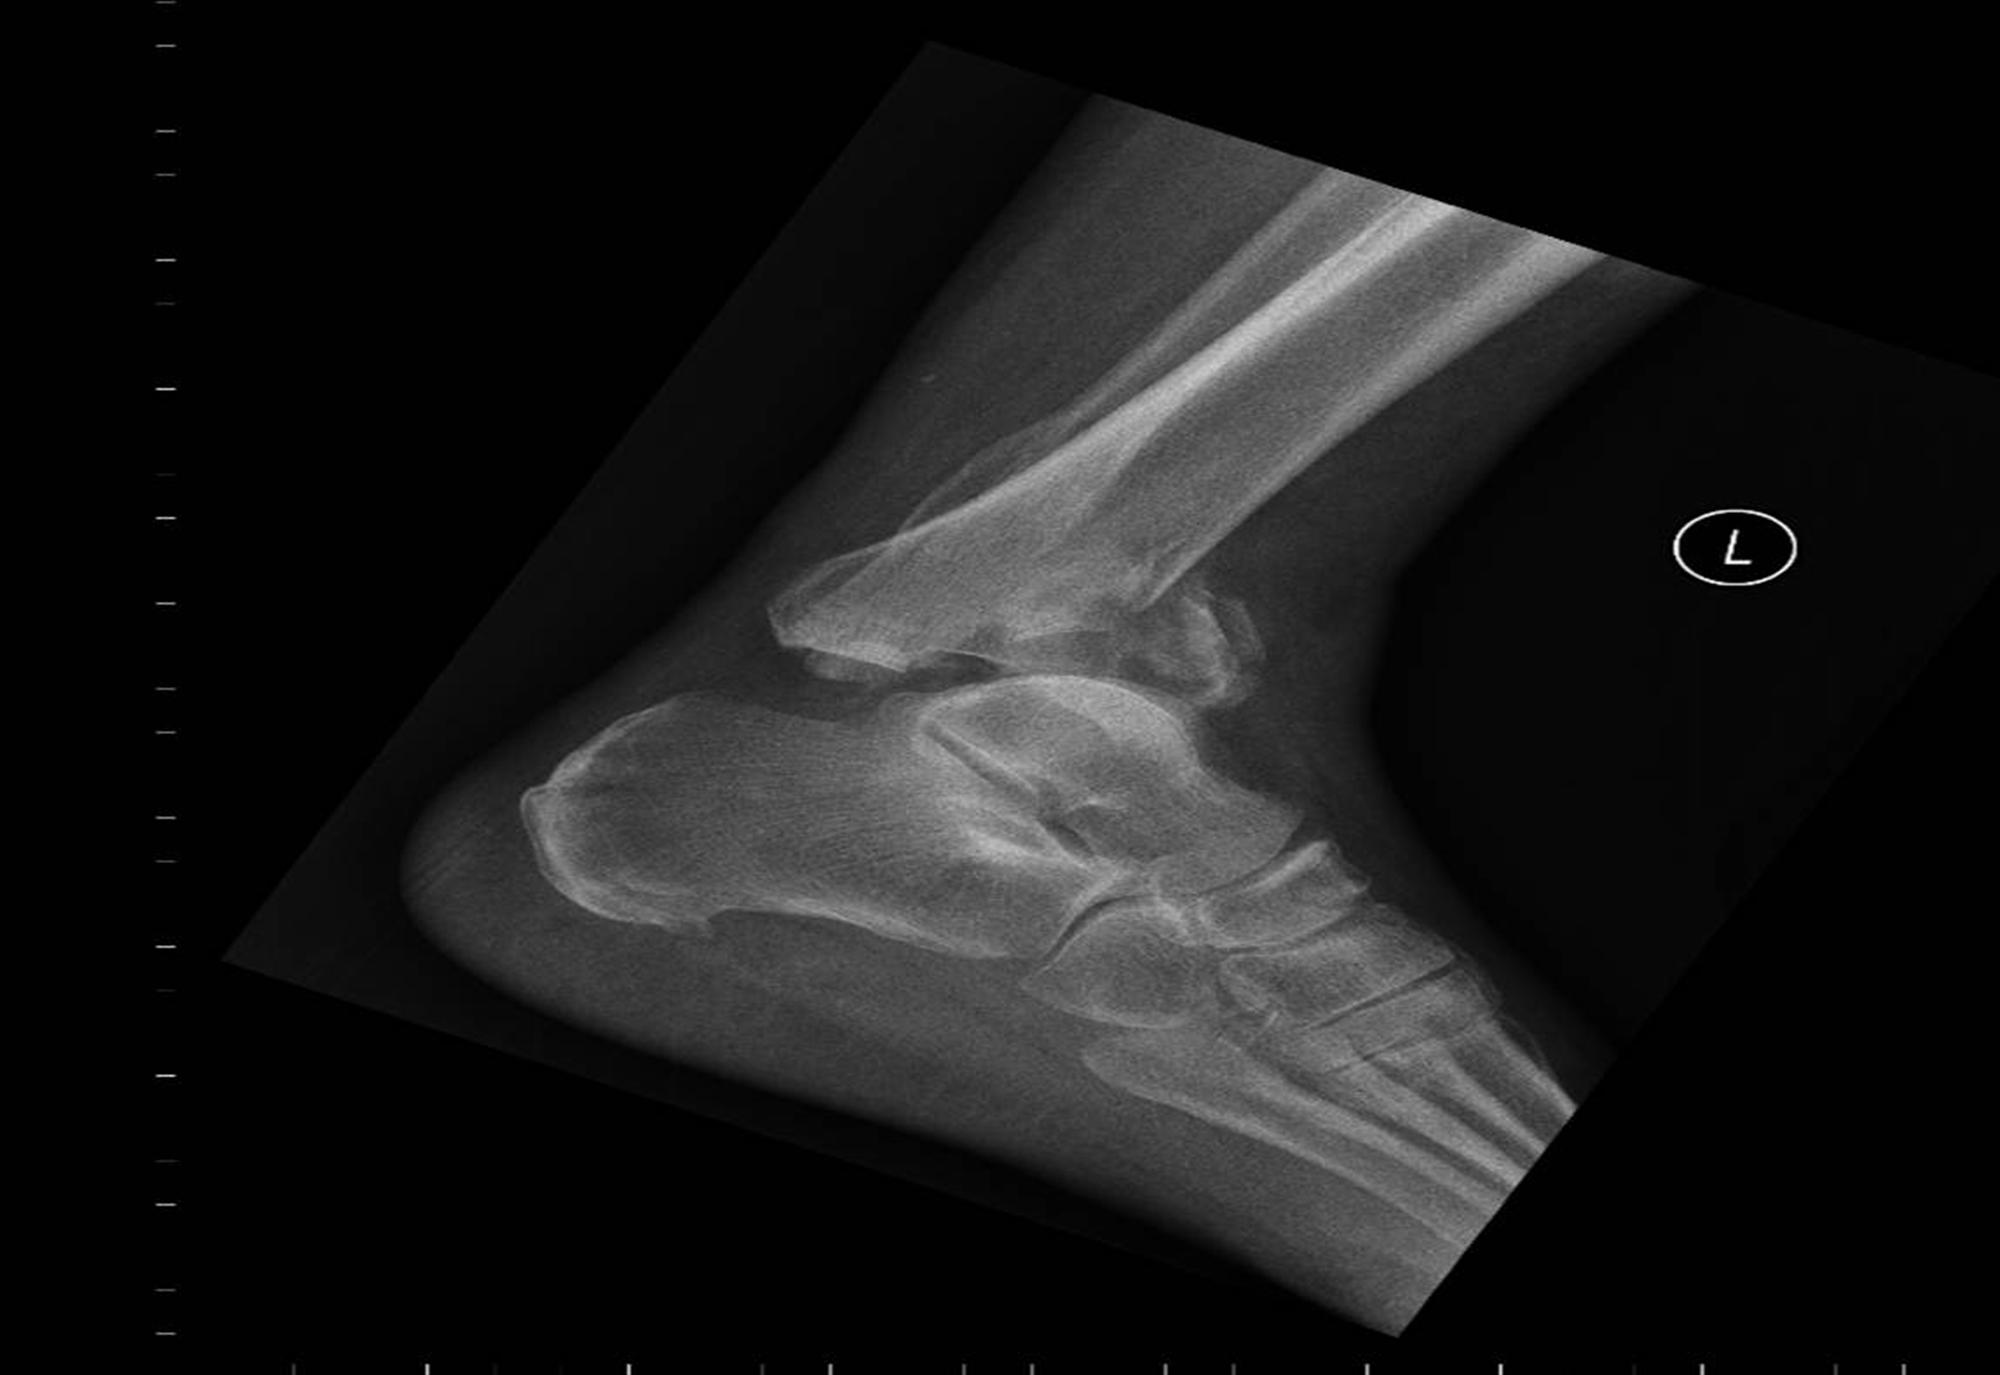

Footballers Ankle Orthobullets . Ankle sprains are the most common injuries in sports and recreational activity, accounting for 40% of all athletic injuries,. He says that prior to symptom development, he was at soccer. Ankle sprains are very common twisting injuries to the ankle that are the most common reason for missed athletic participation. First termed footballer’s ankle by mcmurray in 1950, ami is a common cause of. Diagnosis is made with plain. Chronic ankle pain in football players is most frequently caused by formation of talar and/or tibial osteophytes at the anterior part of. Diagnosis can be made clinically with swelling and. The spurs can form at the bottom end of the joint on the. High ankle sprain & syndesmosis injuries are traumatic injuries that affect the distal tibiofibular ligaments and most commonly occur due to sudden external rotation of the ankle. Ankle fractures are very common injuries to the ankle which generally occur due to a twisting mechanism. Footballer’s ankle, also known as anterior ankle impingement, occurs because bony spurs forms at the front of the ankle joint.

Chronic ankle pain in football players is most frequently caused by formation of talar and/or tibial osteophytes at the anterior part of. Ankle sprains are very common twisting injuries to the ankle that are the most common reason for missed athletic participation. The spurs can form at the bottom end of the joint on the. Diagnosis can be made clinically with swelling and. First termed footballer’s ankle by mcmurray in 1950, ami is a common cause of. Ankle sprains are the most common injuries in sports and recreational activity, accounting for 40% of all athletic injuries,. He says that prior to symptom development, he was at soccer. Footballer’s ankle, also known as anterior ankle impingement, occurs because bony spurs forms at the front of the ankle joint. Ankle fractures are very common injuries to the ankle which generally occur due to a twisting mechanism. High ankle sprain & syndesmosis injuries are traumatic injuries that affect the distal tibiofibular ligaments and most commonly occur due to sudden external rotation of the ankle.

Footballers Ankle Orthobullets First termed footballer’s ankle by mcmurray in 1950, ami is a common cause of. Ankle fractures are very common injuries to the ankle which generally occur due to a twisting mechanism. Ankle sprains are the most common injuries in sports and recreational activity, accounting for 40% of all athletic injuries,. The spurs can form at the bottom end of the joint on the. Diagnosis is made with plain. Diagnosis can be made clinically with swelling and. Chronic ankle pain in football players is most frequently caused by formation of talar and/or tibial osteophytes at the anterior part of. He says that prior to symptom development, he was at soccer. High ankle sprain & syndesmosis injuries are traumatic injuries that affect the distal tibiofibular ligaments and most commonly occur due to sudden external rotation of the ankle. First termed footballer’s ankle by mcmurray in 1950, ami is a common cause of. Ankle sprains are very common twisting injuries to the ankle that are the most common reason for missed athletic participation. Footballer’s ankle, also known as anterior ankle impingement, occurs because bony spurs forms at the front of the ankle joint.